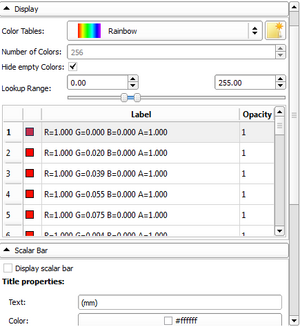

| qMRMLColorTableView |

|

A table view to display a color table model |